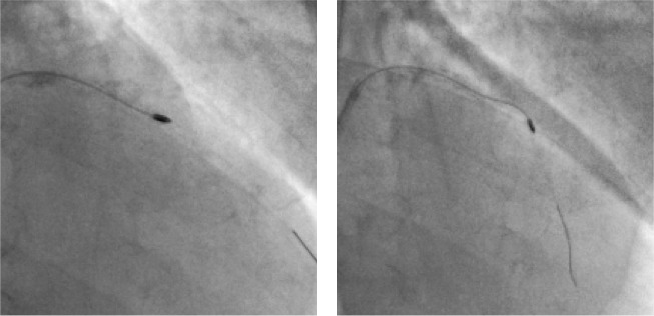

A man with burns on his right hand could not undergo a coronary angiography from the right hand. Dr. Nihar Mehta did his angiography via the distal left radial / snuff box approach, followed by his angioplasty and stenting via the same route. He comfortably walked out of the cath lab subsequently and was discharged 24 hours later.